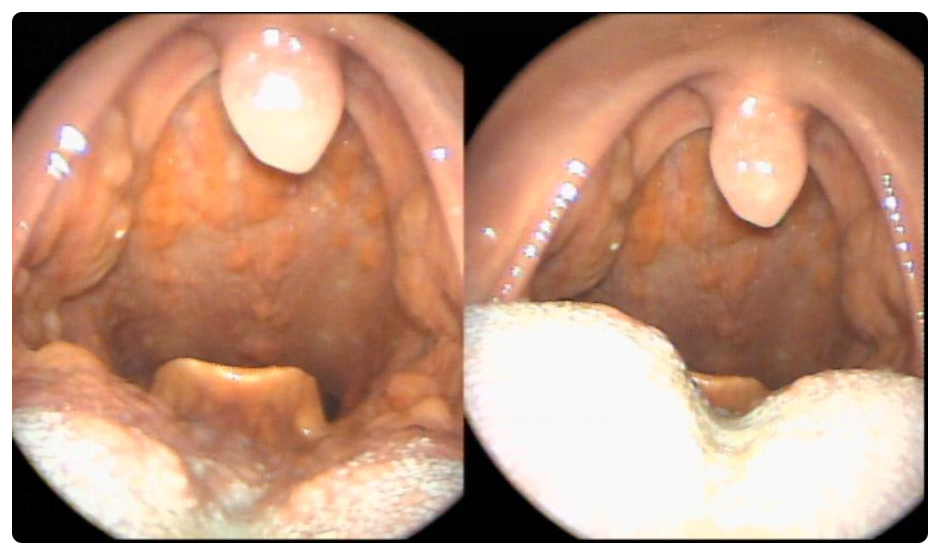

편도의 크기는 크지도 않았고 검사 당시에는 특별히 눈에 띄는 결석도 없었습니다. 크기 1단계로 작은 편입니다.

그렇게 많은 결석은 모두 어디로 갔을까요? 그리고 어디서 나타날까요?사실 눈에 보이는 결석만이 전부는 아닙니다.사실 눈에 보이는 결석만이 전부는 아닙니다. 결석은 편도의 더 깊은 곳에도 있습니다. 또한 편도의 최심부인 편도 중앙에서도 편도 결석이 자랍니다. 결석 제거를 위한 부분적인 편도절제술로 재발이 많은 이유가 그 때문입니다. 바깥쪽 편도 봉투를 자른 곳에서 안쪽에서 다시 바로 나옵니다.

편도결석이란? 편도결석은 건락성(cheesy)이 하얗거나 노란색 1cm 이내의 물질로 나타나며 구취(halitosis)와 인후통, 목물감 등을 동반하기도 합니다.

이 환자의 경우 심부 60% 정도에 이르기까지 편도 내에 다량의 결석이 존재하고 있었습니다. 수술하면서 편도를 잡고 누를 때 상당한 양의 편도 결석이 밖으로 튀어나왔습니다.